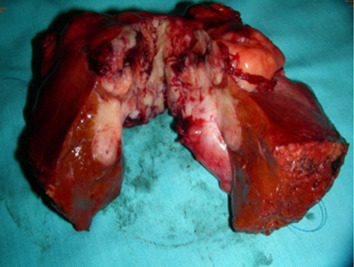

A 52-year-old female patient presented with postprandial epigastric pain that had persisted for 1 year. The pain was mild and improved after antacid treatment. She was seen at our hospital after being diagnosed with a hepatic tumor at a local clinic. Abdominal ultrasonography revealed one mixed echogenic tumor approximately 9.5 cm from the gallbladder sac and extending to S4–5 of the liver. The common bile duct was dilated to 1.4 cm (Fig. 1). Liver function tests and total bilirubin levels were within the normal range. However, carbohydrate antigen 19-9 (CA 19-9) was elevated to 60.9 U/mL. A follow-up abdominal computed tomography (CT) confirmed a 7.5 cm sized gallbladder cancer with liver invasion (Fig. 2), consistent with clinical Stage III cancer according to the TNM system (tumor-node-metastasis classification system).

Abdominal ultrasonography showing one mixed echogenic tumor approximately 9.5 cm ...

Figure 1.

Abdominal ultrasonography showing one mixed echogenic tumor approximately 9.5 cm from the head of the gallbladder sac. The common bile duct was dilated to 1.4 cm.